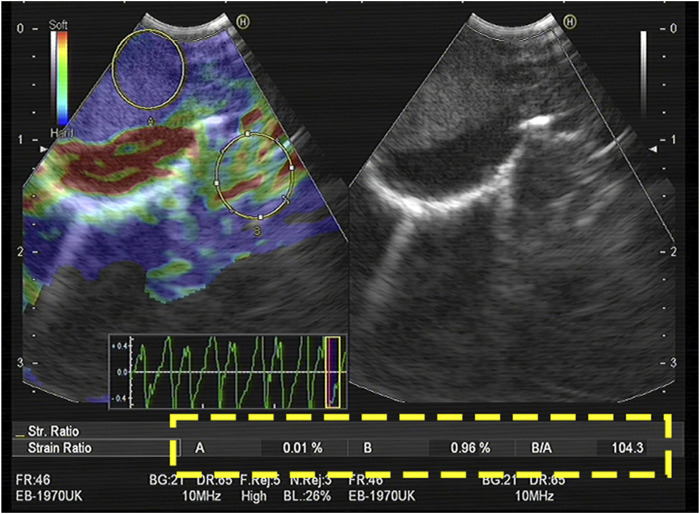

目的:在恶性肿瘤中,弹性成像和血清肿瘤标志物显示出很高的诊断效力。因此,我们旨在定量分析肺癌支气管内弹性成像结合血清肿瘤标志物的结果,以准确区分纵隔和肺门淋巴结的良恶性。研究方法回顾性收集2018年1月至2022年8月期间在我院接受支气管内超声引导下经支气管针吸术治疗纵隔淋巴结肿大的患者资料。评估定量弹性成像和血清肿瘤标志物的特征。结果:我们共收治了197名患者(273个淋巴结)。在纵隔和肺门淋巴结的良恶性鉴别诊断中,淋巴结的硬度面积比(SAR)、应变比(SR)和应变率均有显著意义,其中SAR的诊断价值最高(临界值为0.409)。四种肿瘤标记物的组合具有很高的诊断价值(AUC,0.886)。三种定量弹性成像指数与血清肿瘤标志物相结合对肺癌的诊断价值更高(AUC,0.930;敏感性,83.5%;特异性,89.3%;阳性预测值,88.1%;阴性预测值,85%)(P < 0.05)。在肺癌病理类型的鉴别诊断中,不同的肺癌定量弹性成像指标和血清肿瘤标志物对肺癌病理类型的鉴别诊断具有不同的诊断意义。结论支气管内超声弹性成像定量分析结合肿瘤标志物可提高纵隔及肺门淋巴结良恶性诊断率,有助于指导假阴性淋巴结的穿刺,降低误诊率。

Purpose: In malignant tumours, elastography and serum tumour markers have shown high diagnostic efficacy. Therefore, we aimed to quantitatively analyse the results of endobronchial elastography combined with serum tumour markers of lung cancer to accurately distinguish benign and malignant mediastinal and hilar lymph nodes. Methods: Data of patients who underwent endobronchial ultrasound-guided transbronchial needle aspiration for mediastinal lymph node enlargement in our hospital between January 2018 and August 2022 were retrospectively collected. The characteristics of quantitative elastography and serum tumour markers were evaluated. Results: We enrolled 197 patients (273 lymph nodes). In the differential diagnosis of benign and malignant mediastinal and hilar lymph nodes, the stiffness area ratio (SAR), strain ratio (SR), and strain rate in lymph nodes were significant, among which SAR had the highest diagnostic value (cut-off value, 0.409). The combination of the four tumour markers had a high diagnostic value (AUC, 0.886). Three types of quantitative elastography indices combined with serum tumour markers for lung cancer showed a higher diagnostic value (AUC, 0.930; sensitivity, 83.5%; specificity, 89.3%; positive predictive value, 88.1%; negative predictive value, 85%) (p < 0.05). In the differential diagnosis of pathological types of lung cancer, different quantitative elastography indicators and serum tumour markers for lung cancer have different diagnostic significance for the differential diagnosis of lung cancer pathological types. Conclusion: The quantitative analysis of endobronchial ultrasound elastography combined with tumour markers can improve the diagnosis rate of benign and malignant mediastinal and hilar lymph nodes, help guide the puncture of false negative lymph nodes, and reduce the misdiagnosis rate.